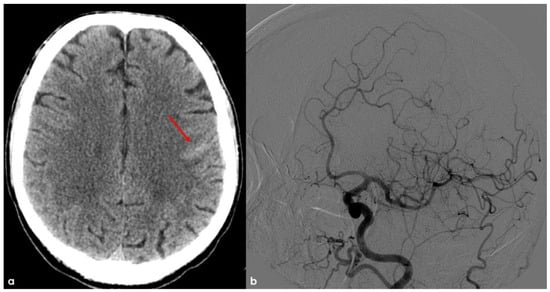

2. December 2013: Sulcal SAH and TFNEs

4. December 2015: Ischemic Stroke

6. December 2017: Recurrent SAH